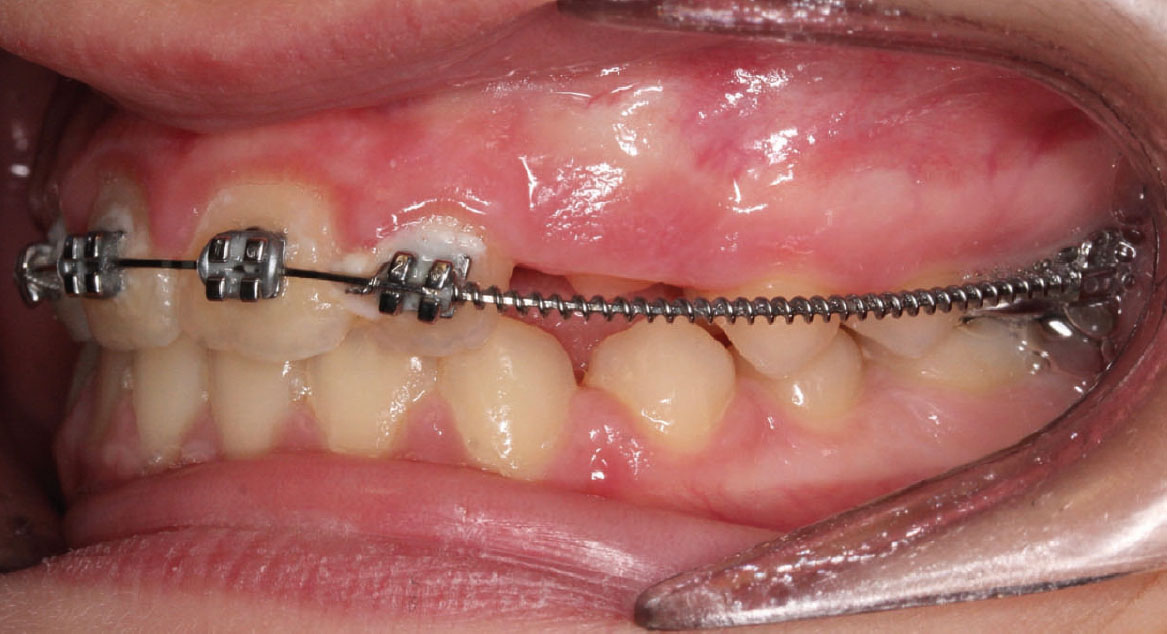

Bandaggio e sequenza archi

A tre mesi dalla cementazione dell’ERP si programma il bandaggio parziale superiore da 12 a 22 (Mini Master, prescrizione MBT, slot 22×28, American orthodontics) posizionando in maniera strategica i bk su 12 e 22, per il controllo del tip ed evitare interferenza con il tragitto eruttivo di 13 e 23. Sono state posizionate delle open coil attive e arco 016 Tanzo (fig. 8).

Fig. 8A Terapia intercettiva con REP e bandaggio parziale superiore.

Fig. 8B Terapia intercettiva con REP e bandaggio parziale superiore.